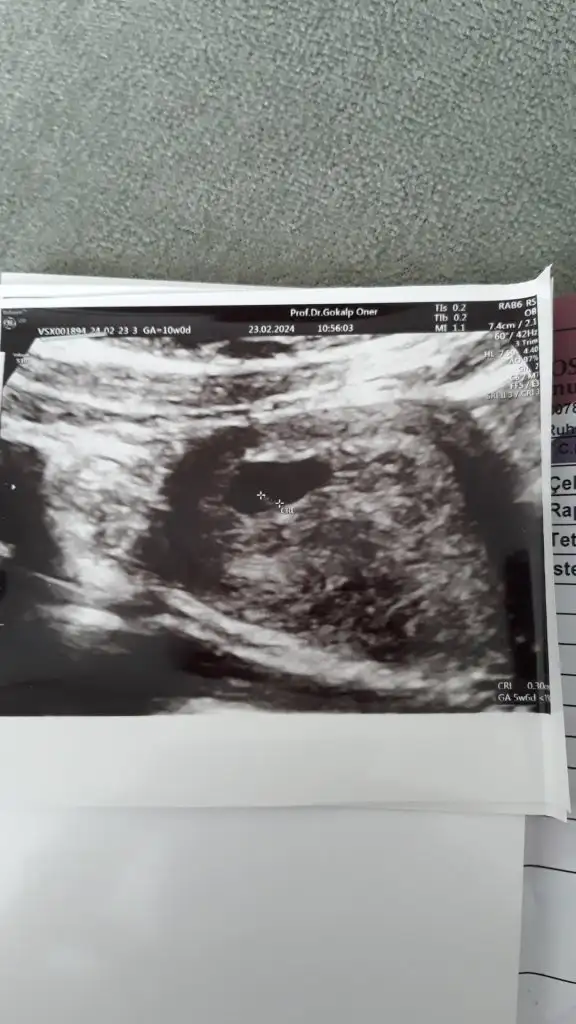

Merhaba kızlar mutlu haberlerle gelemedim maalesef bugün kalp atışını duyamadık doktor 1 hafta daha bekleyelim dedi ama benim hic ümidim yok açıkçası cok üzgünüm.ultrasonu da ekliyorum belki anlayan biri vardır.kese de 19.5 mm mis

Canim alttan mi bakiyor ustten mi alttan isteseydin ustten gec oluyormus canim uzulme hemen kotu dusunmeyelim kac haftalik bebisin

5+6 gözüküyor günü. Biraz erken olabilir bence , daha çok küçük değil mi